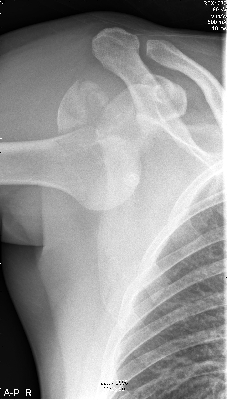

Na de ongelukige val was de arm uit de kom. |

Nadat deze was terug gezet zag het er weer goed uit. |